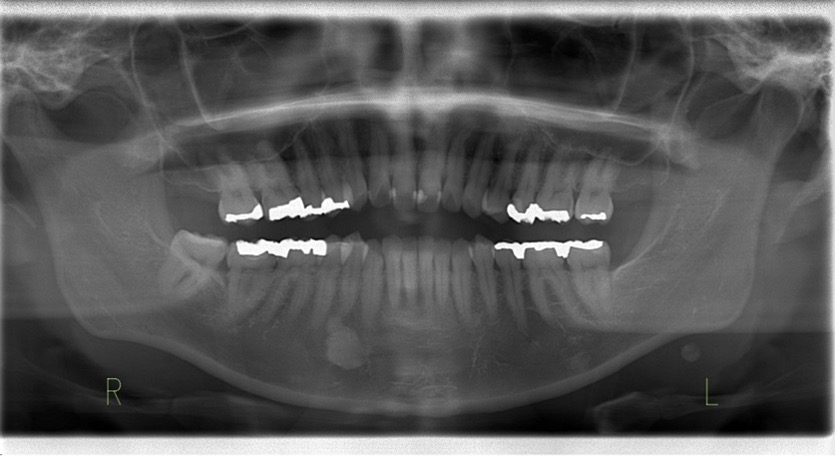

パノラマX線・レントゲン写真

下顎:メタルインレーが複数装着